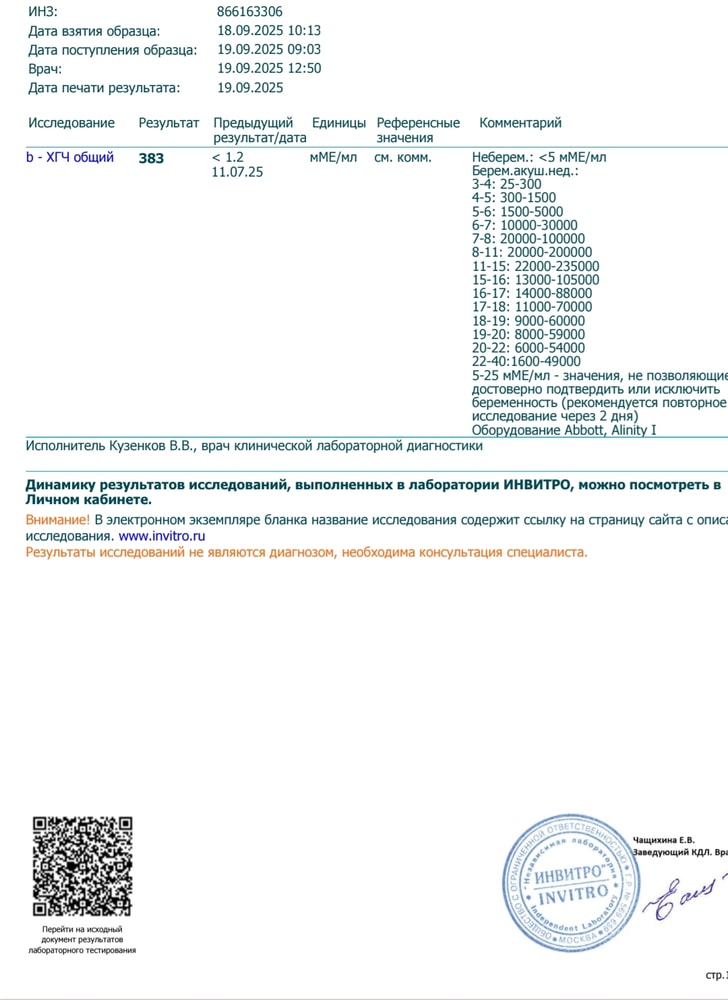

Обследования, узи, анализыТесты показывают "сомнительно" Положительную беременность

Ну тут вообще не сомнительно, у вас четкие полоски , сдайте ХГЧ и отслеживайте рост, когда будет больше 1000 или те на узи)

Сомнительный результат теста может быть связан с несколькими факторами - уровень хорионического гонадотропина может быть ещё слишком низким, либо есть ложноположительная реакция. Кисты в эндометрии иногда влияют на гормональный фон и могут давать подобные ситуации. Лучше сдать кровь на ХГЧ и пройти повторное УЗИ через несколько дней, чтобы отследить динамику.

Сдать хгч в динамике,думаю это беременность,просто на узи еще не видно,т к рано